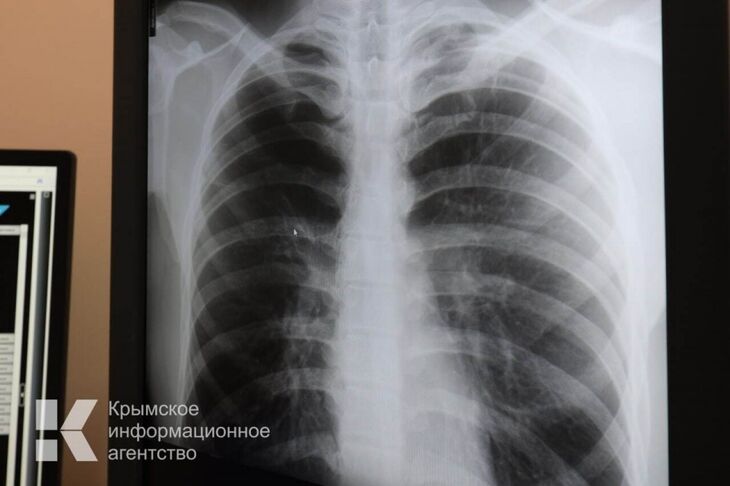

24 марта с 09:00 до 14:00 по адресу ул. Пушкина, д.3 жители и гости полуострова смогут пройти бесплатное флюорографическое обследование на передвижном мобильном комплексе.

Акцию проведут ГБУЗ РК «Крымский республиканский клинический центр фтизиатрии и пульмонологии», ГБУЗ РК «Центр общественного здоровья и медицинской профилактики», КРО ВОД «Волонтеры-медики» при поддержке Министерства здравоохранения Республики Крым.